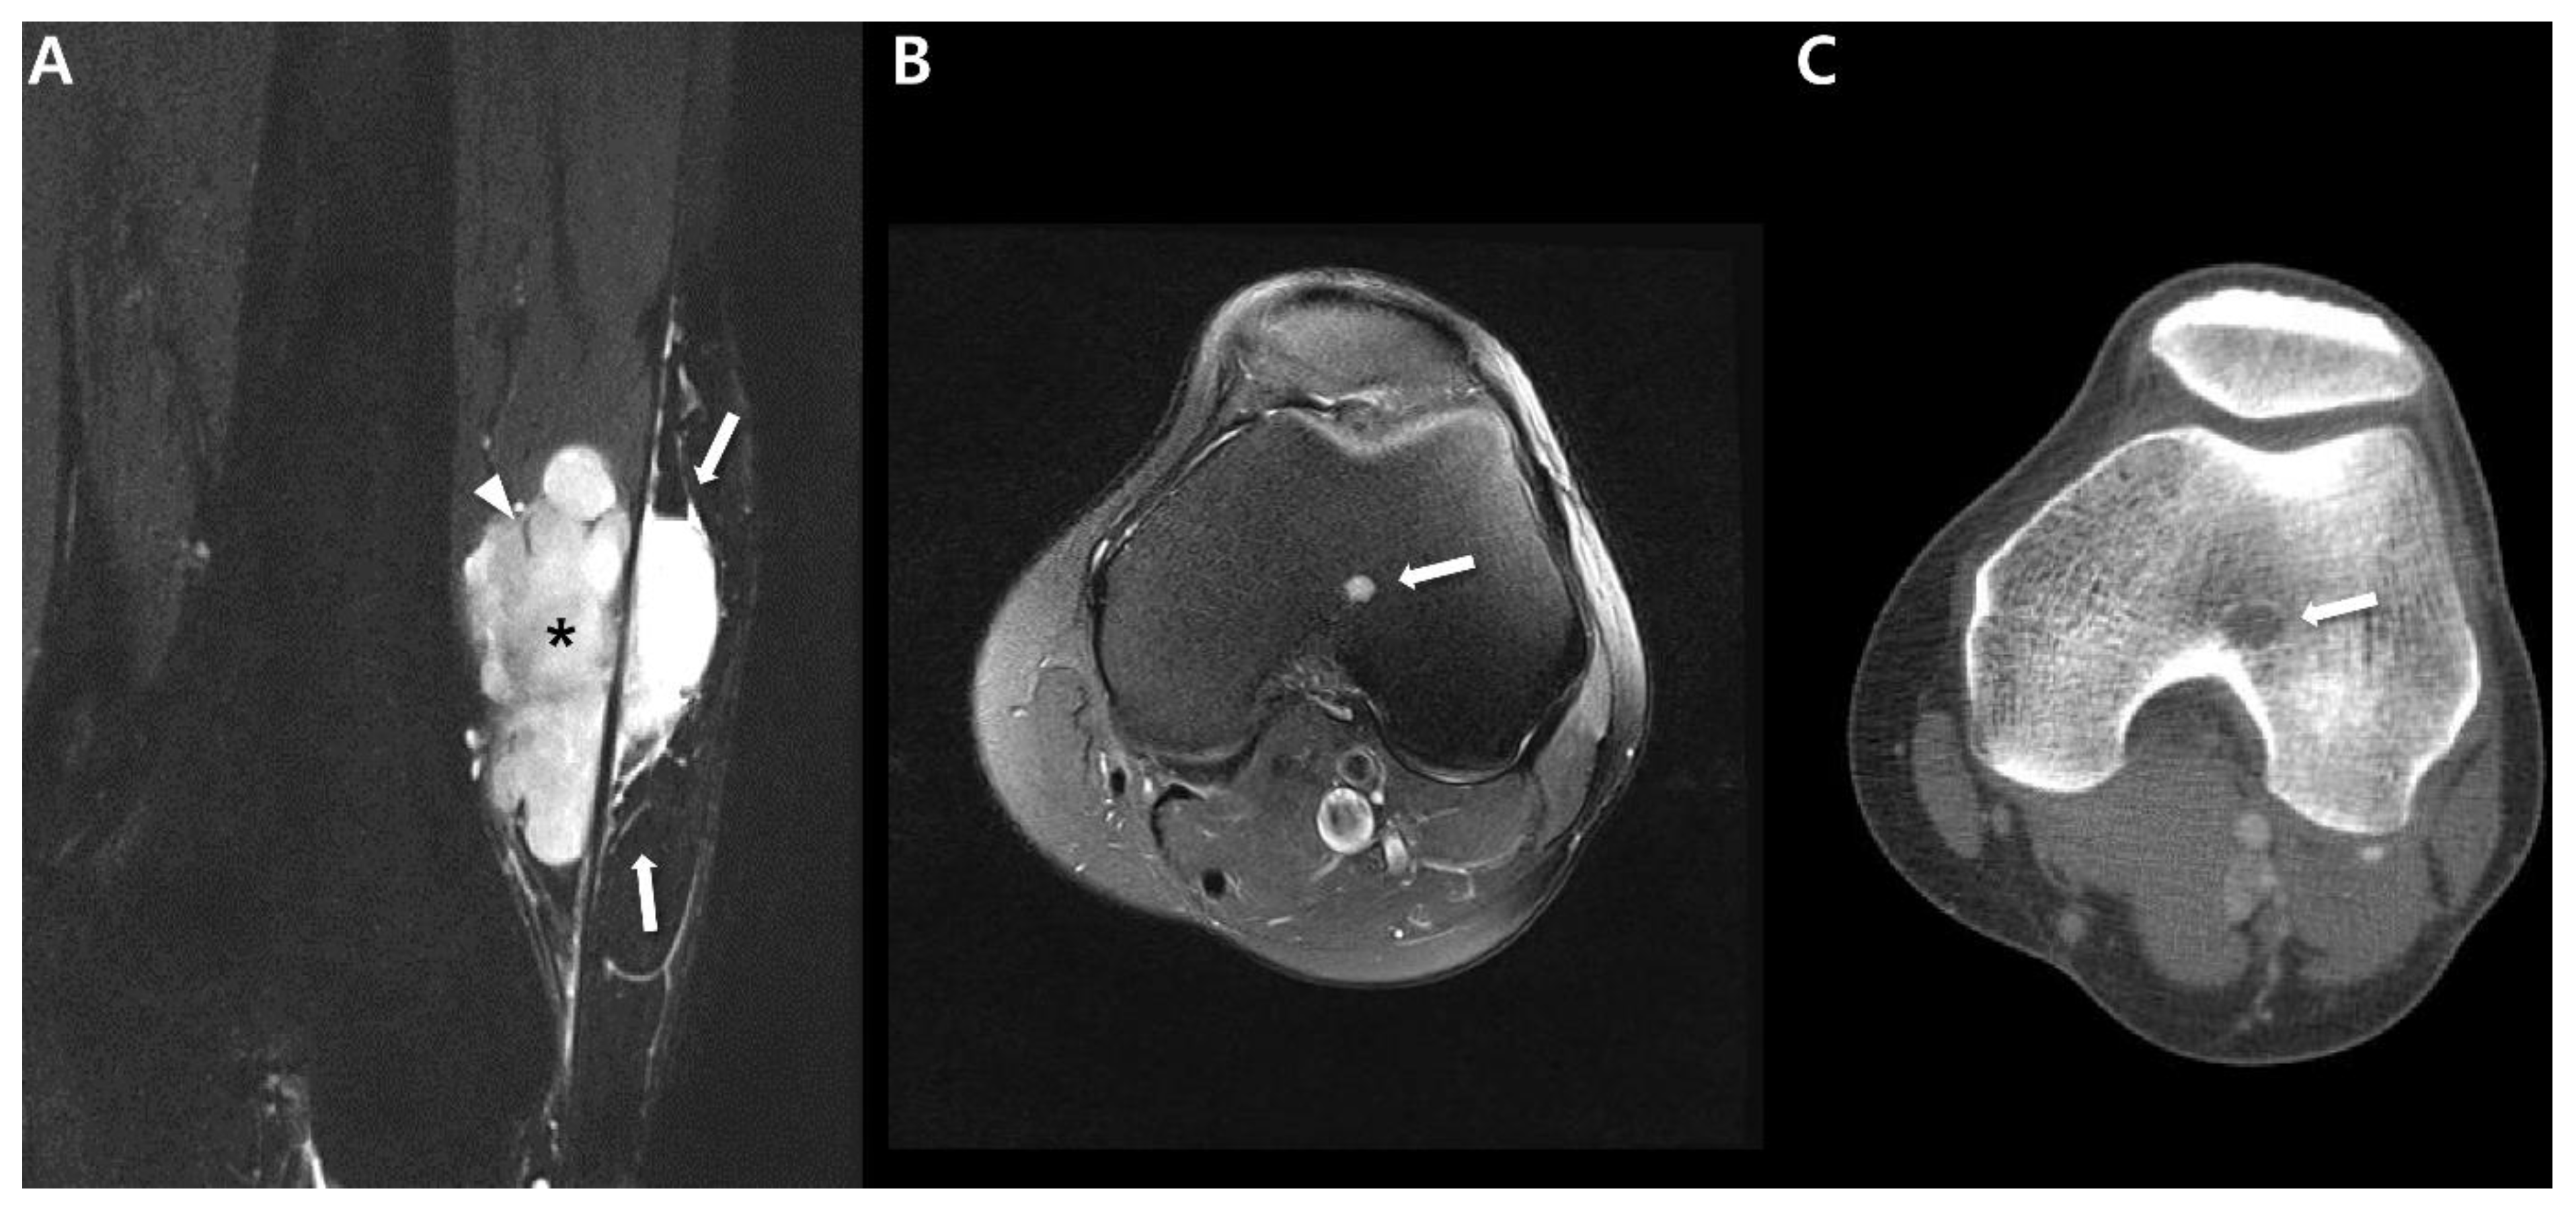

2.3. Ultrasound

2.4. Magnetic Resonance Imaging (MRI)

3. Uncommon Primary Sites of Synovial Sarcoma in the Extremities